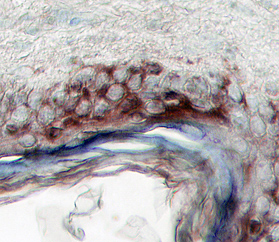

Vanilloid R-like 3/TRPV3 in Human Skin. Vanilloid R-like 3/TRPV3 was detected in immersion fixed paraffin-embedded sections of human skin using 15 µg/mL Human Vanilloid R-like 3/TRPV3 Antigen Affinity-purified Polyclonal Antibody (Catalog # AF4167) overnight at 4 °C. Tissue was stained with the Anti-Goat HRP-DAB Cell & Tissue Staining Kit (brown; Catalog # CTS008) and counterstained with hematoxylin (blue). View our protocol for Chromogenic IHC Staining of Paraffin-embedded Tissue Sections.